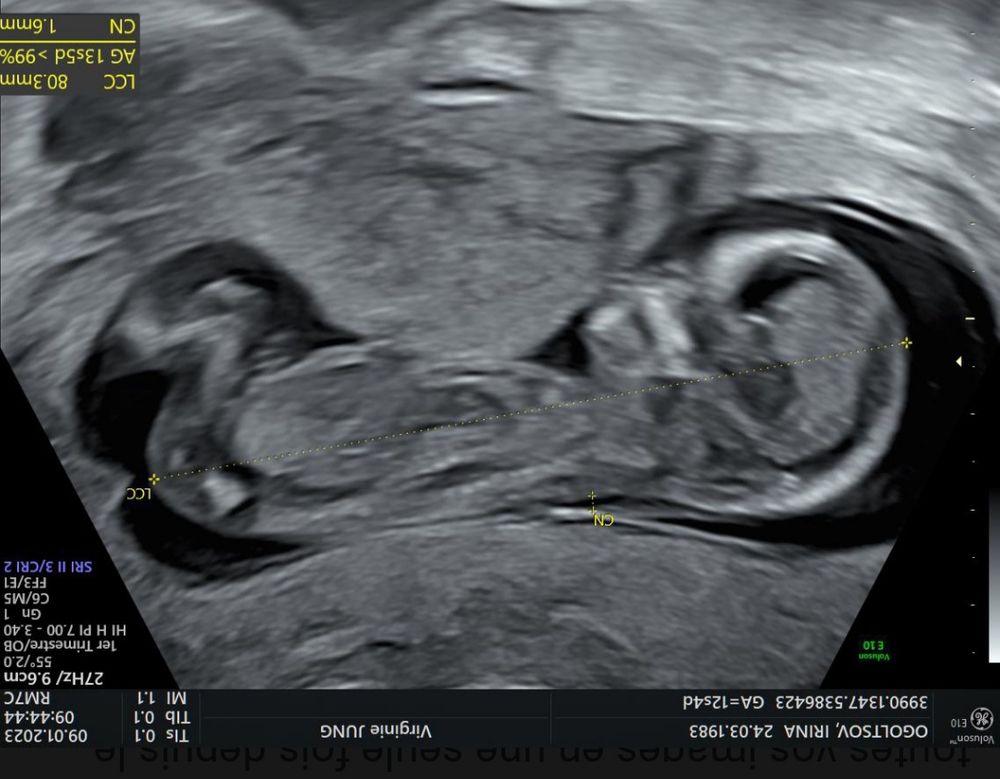

Ну точно Вам скажут только после 20 недели, а вообще сестре моего мужа до последнего говорили что мальчик, и американский тест говорил, а потом уже ближе к сроку разглядели девчушку. А сестра мужа говорит; мы вообще-то мальчика ждём 😂 но как бы там ни было не надо печалиться, главное здоровье малыша, а дочь может быть в виде внучки придёт, всякое бывает - это жизнь